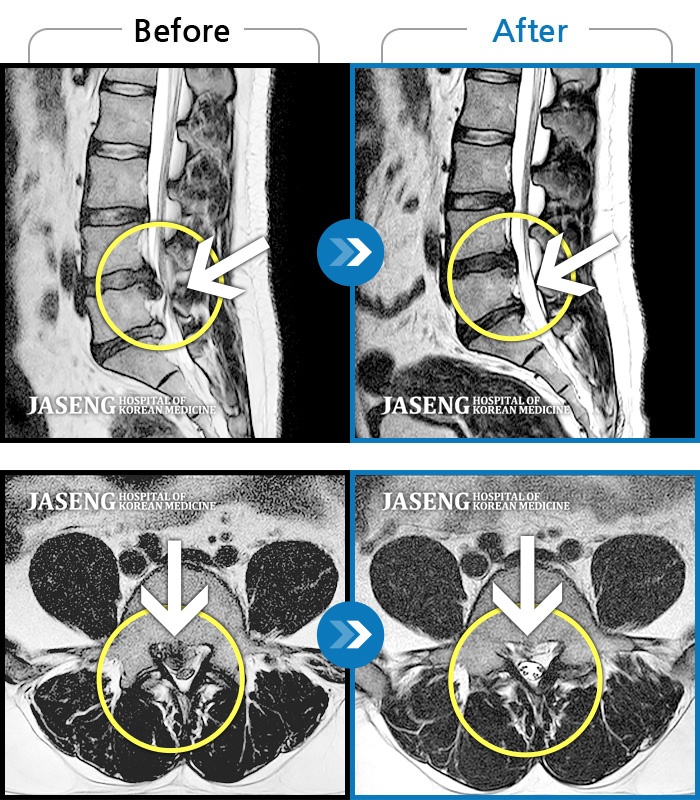

목디스크

천안 · 윤영웅 원장

왼쪽 목, 어깨, 등 통증과 팔저림이 심해서 잠을 못자요.

촬영시기

2021.11.20 ~ 2022.11.17

2022.11.25